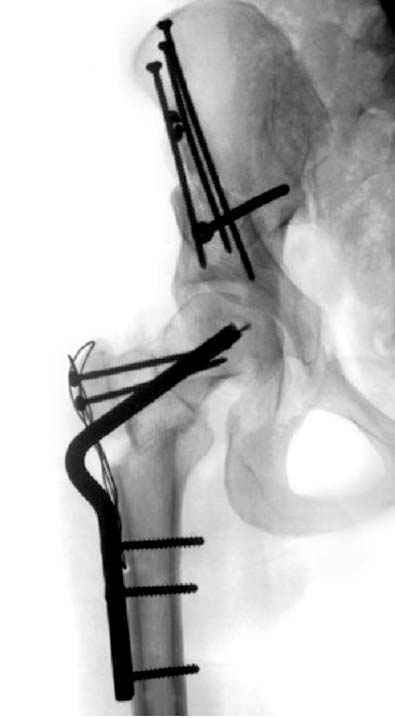

Рис.1 Трехмерная модель тазобедренного сустава с аналогом связки головки бедра. Заметно, что из торца головки выходит капроновый шнур, который с одной стороны прикрепляется к ножке бедренной части модели, а другой его конец, проходя через головку и прикрепляется к вертлужной части модели. Динамометр оказывается не нагруженным, так как аналог связки головки бедра замыкает подвижный узел модели во фронтальной плоскости.

|

Рис.2 Та же трехмерная модель тазобедренного сустава без аналога связки головки бедра. Пружина динамометра удерживает тазовую часть модели от опрокидывания, поддерживая стабильность так же, как отводящие мышцы обеспечивают ее в отсутствии связки головки бедра.